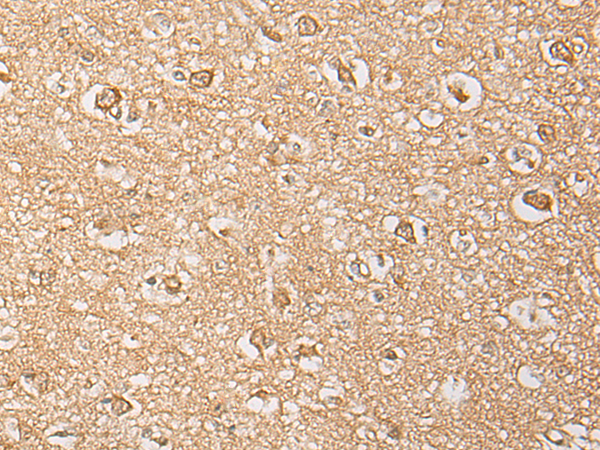

分类: 科研抗体货号: P06324别名: GRFR; GHRFR; IGHD1B应用: IHC反应种属: Human